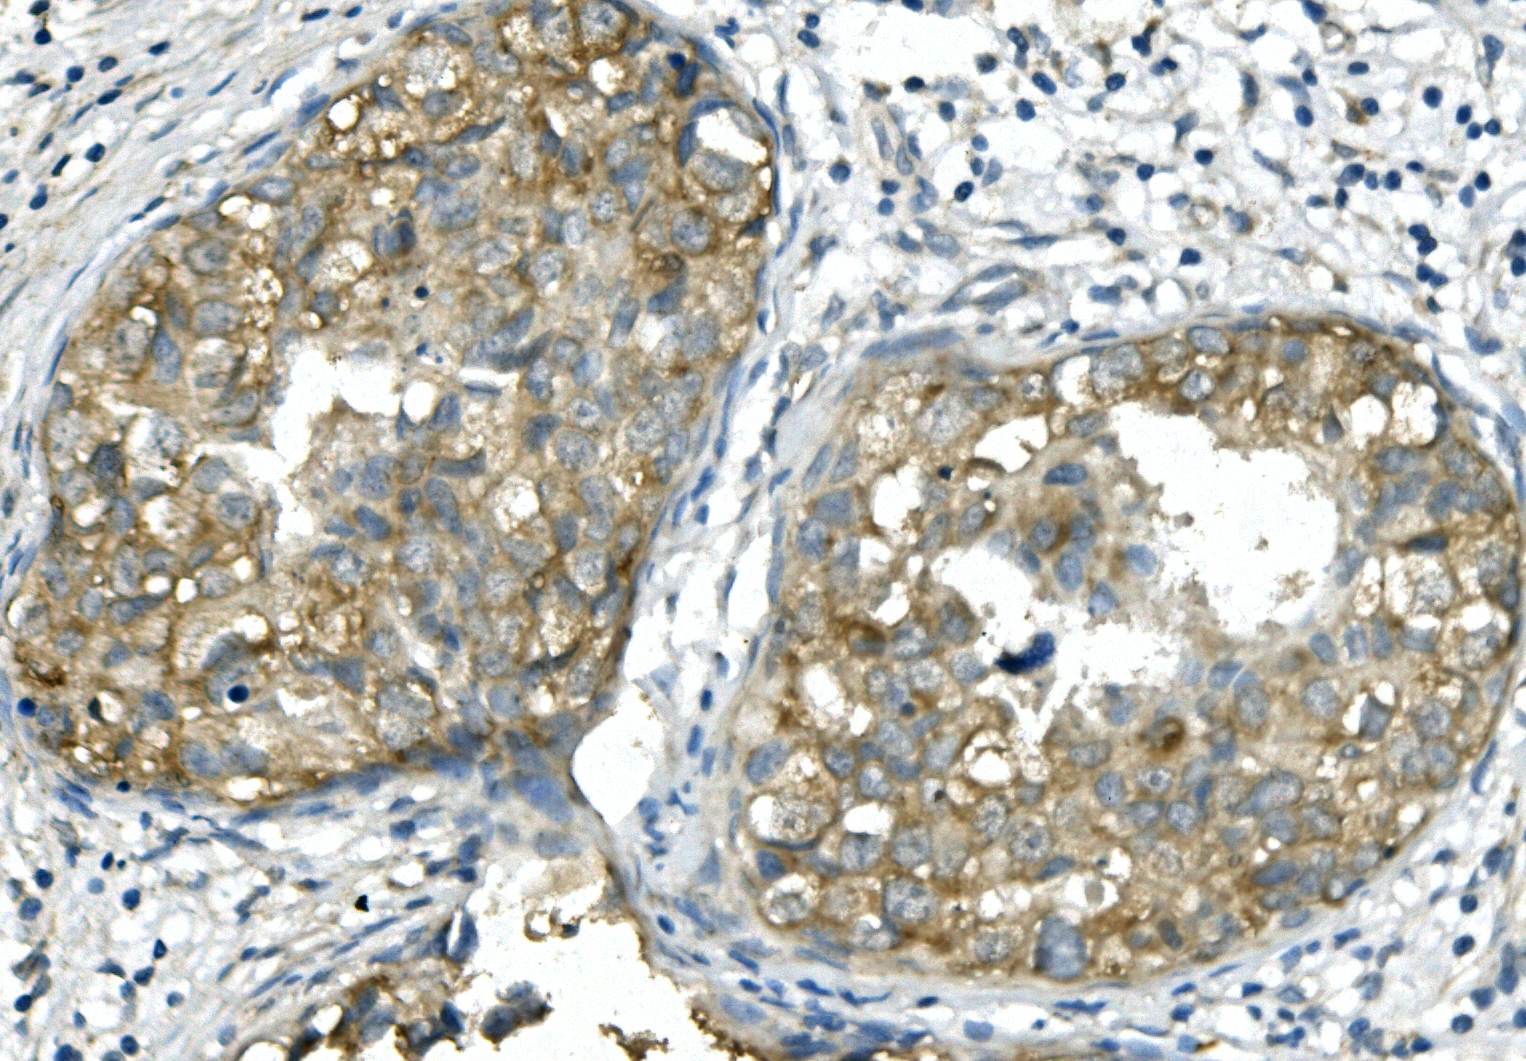

IHC analysis of BubR1/BUB1B using anti-BubR1/BUB1B antibody (M01564-3).

BubR1/BUB1B was detected in a paraffin-embedded section of human mammary cancer tissue. Biotinylated goat anti-mouse IgG was used as secondary antibody. The tissue section was incubated with mouse anti-BubR1/BUB1B Antibody (M01564-3) at a dilution of 1:200 and developed using Strepavidin-Biotin-Complex (SABC) (Catalog # SA1021) with DAB (Catalog # AR1027) as the chromogen.